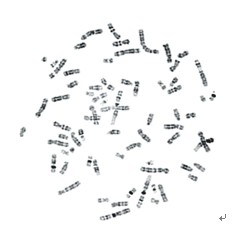

BandView染色體條帶分析系統(tǒng)

型號:BandView